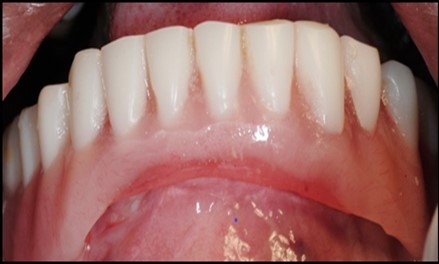

Figure 12.Insertion of the lower denture

Insertion of the lower denture

General criteria for survival and success of implants have been used to evaluate the efficacy of immediately loading mandibular implants. For example, survival criteria include how the implant performs, particularly regarding the absence of pain, infection, and paresthesia. Implant immobility and the absence of periimplant radiolucency under radiography are 2 more criteria of implant survivability.6, 7 Success criteria include the additional element of absence of vertical bone loss; specifically, less than 1 mm during the first year and less than 0.2 mm annually thereafter. Granted that success rates for immediatel oading of implants in the edentulous mandible are not as high as rates for the traditional 2-stage approach, conditions nevertheless often warrant the 1-stage surgical option described here.7, 8, 9 (Figure 12).

Using 2 implants and retentive anchors for the retention of a mandibular complete denture is, in terms of immediate costs, one of the most affordable implant procedures. 8, 9, 14 With ideal placement of the implant, the stability of the prosthesis is excellent and the lingual dimensions of the denture can in some cases be reduced to the level of mylohyoid line, providing more space for the tongue and greater comfort than with conventional complete dentures.8, 9, 10, 15 However, if the labial musculature is tense or the amount of attached gingiva is limited, the implants should not be placed too deep or too labially, which might prevent gingival growth over the abutments. In those cases, ball anchor abutments with elevated shoulders can be used to improve implant anatomy.8, 9, 10 (Figure 12).